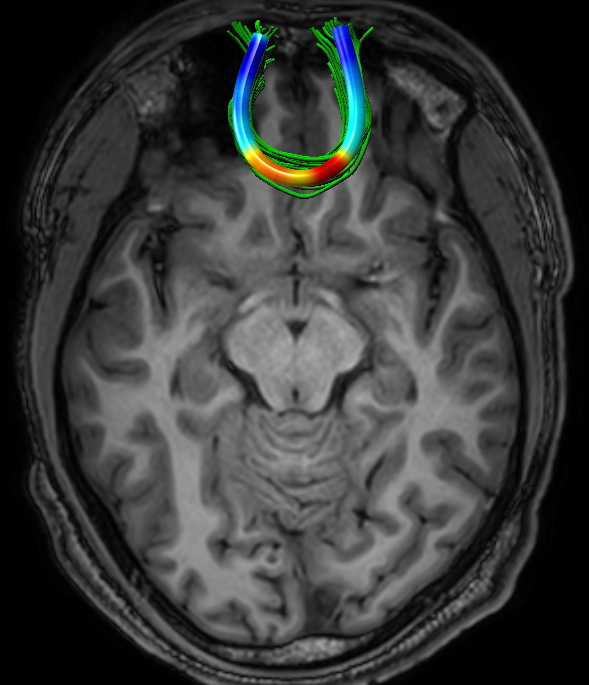

We performed pairwise comparison between two scans of a 32-year-old basketball player, diagnosed with mild occipital traumatic brain injury and frontal hemorrhage due to contrecoup impact, acquired one week and 6 months post-injury. The hemorrhagic lesion at the frontal right hemisphere of the player is no longer visible in the FLAIR image acquired 6 months after injury (Fig. 2a). Local differences between corresponding, longitudinal FA- and MD-FFDD profiles of the FMT (chosen due to its proximity to the lesion area) are shown in Fig. 2d. Figs. 2b-c present color-coded FMT to visually demonstrate these differences. Results show significant longitudinal variability at the right hemisphere part of the tract, corresponding to the lesion area, and relatively minor differences along the rest of the tract. These results should be considered as a proof of concept, validating the FFDD analysis results for the detection and localization of mTBI-related variabilities between fiber bundles.

| ONE WEEK | ![]() |

![]() |

FA-FFDD |

| 6 MONTHS | ![]() |

MD-FFDD |

| (a) FLAIR | (b) FA-FFDD | (c) MD-FFDD | (d) Local Differences |